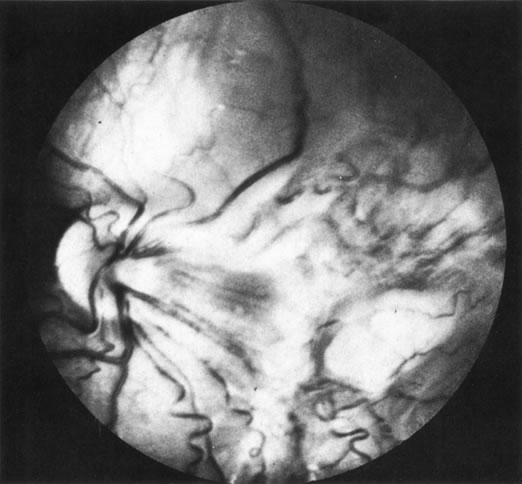

1. The intraocular findings in primary intraocular–CNS lymphoma may simulate a diffuse uveitis, usually with a plethora of vitreous cells and often with virtually pathognomonic yellowish white chorioretinal infiltrates (Fig. 20). Less common clinical presentations can mimic toxoplasmosis, acute retinal necrosis, a branch vein occlusion, or various forms of retinal vasculitis.

Fig. 20. Yellowish white chorioretinal infiltrate typical of primary intraocular lymphoma (erroneously termed ocular reticulum cell sarcoma). (Char DH: Clinical Ocular Oncology. 2nd ed. Philadelphia, Lippincott-Raven, 1996.)